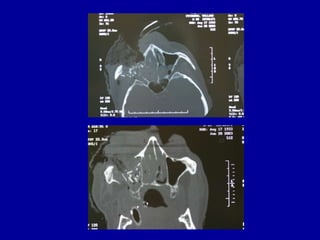

Radiographic Evaluation

• Decisions on radiographic evaluation

needed are based on findings in clinical

exam

• CT- axial, coronal, and 3D reconstruction

CT vs plane films

• CT has become the standard of care where

available, for evaluation of midface skeletal

trauma

• Both have strengths and weaknesses, but

plane films are rarely ordered today